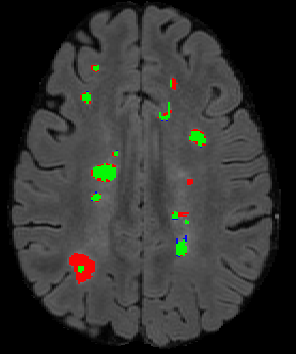

The detection of new multiple sclerosis (MS) lesions is an important marker of the evolution of the disease. The applicability of learning-based methods could automate this task efficiently. However, the lack of annotated longitudinal data with new-appearing lesions is a limiting factor for the training of robust and generalizing models. In this work, we describe a deep-learning-based pipeline addressing the challenging task of detecting and segmenting new MS lesions. First, we propose to use transfer-learning from a model trained on a segmentation task using single time-points. Therefore, we exploit knowledge from an easier task and for which more annotated datasets are available. Second, we propose a data synthesis strategy to generate realistic longitudinal time-points with new lesions using single time-point scans. In this way, we pretrain our detection model on large synthetic annotated datasets. Finally, we use a data-augmentation technique designed to simulate data diversity in MRI. By doing that, we increase the size of the available small annotated longitudinal datasets. Our ablation study showed that each contribution lead to an enhancement of the segmentation accuracy. Using the proposed pipeline, we obtained the best score for the segmentation and the detection of new MS lesions in the MSSEG2 MICCAI challenge.